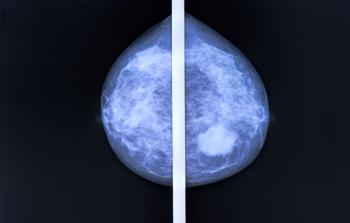

CDK4/6 inhibitors have demonstrated promise in treating patients with estrogen receptor (ER)–positive, HER2-negative breast cancer in both a neoadjuvant and adjuvant setting.